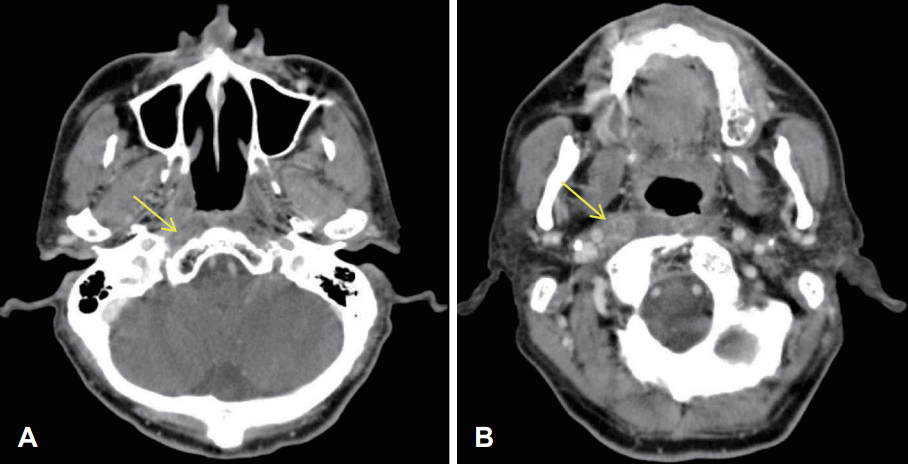

Fig. 3.

CT axial views after being treated with IMRT and chemotherapy, Contrast enhanced CT axial image shows (arrow) (A) intact nasopharynx, implying no recurrence of cancer (B) retropharyngeal lymph nodes with asymmetric soft tissue lesion suspicious of post treatment change rather than residual tumor (arrow). IMRT: intensity modulated radiation therapy.